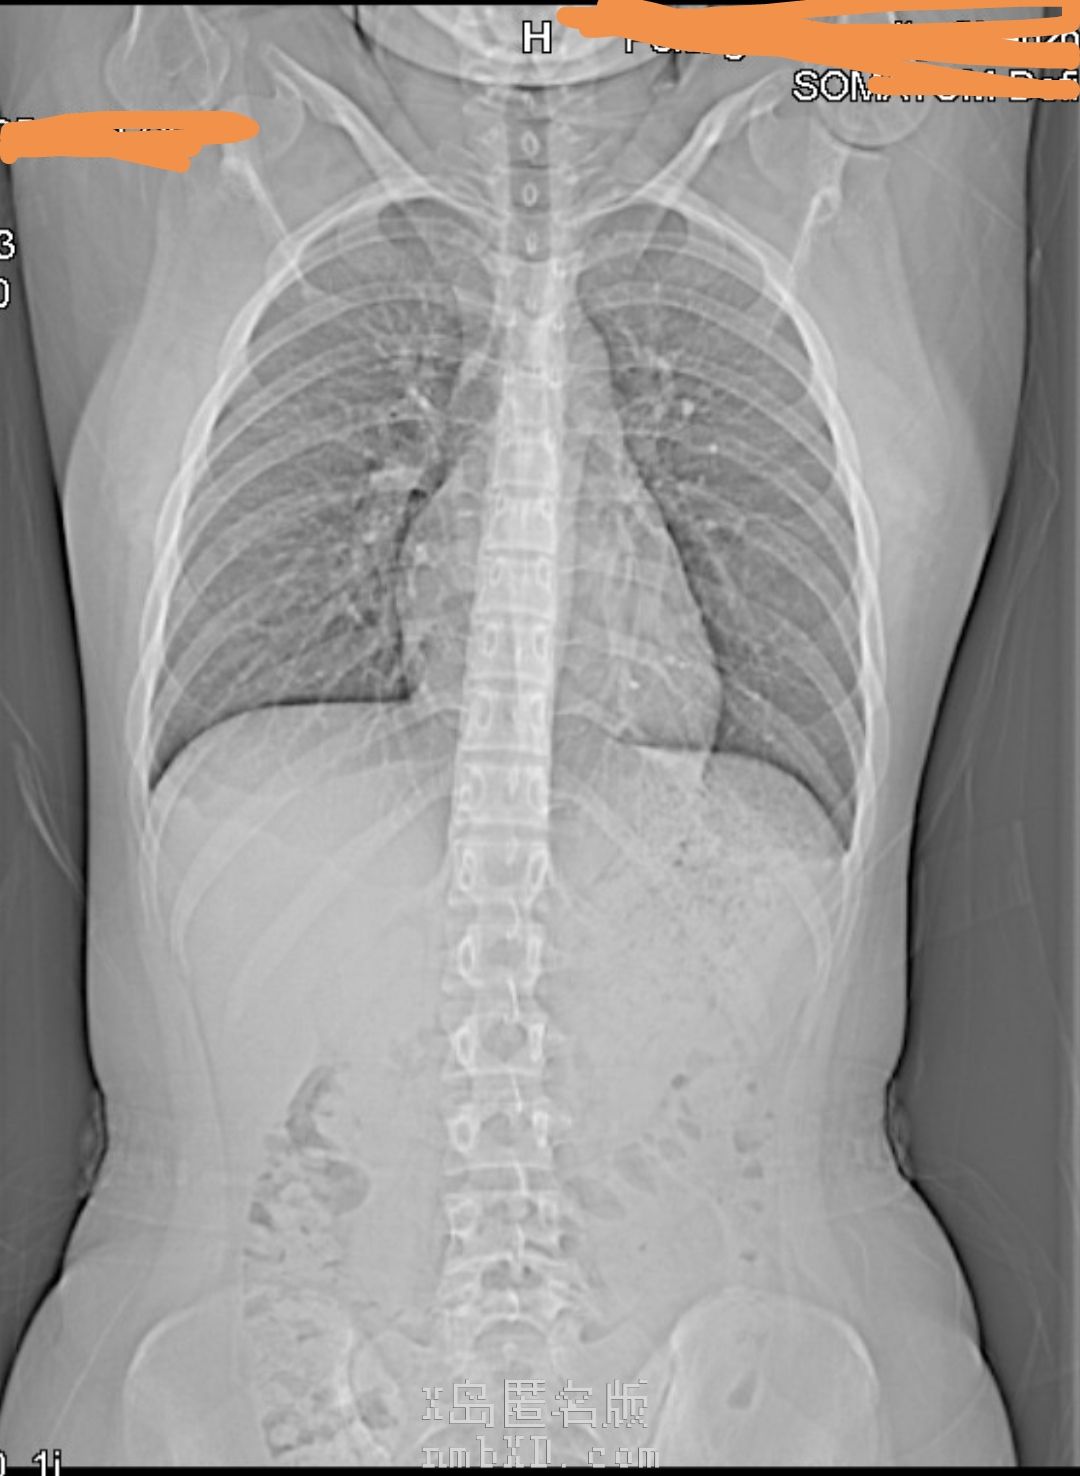

报告!手上目前只有这个胸椎CT!(感觉是不是看不出来什么)(*´д`)

确实看不太出来,但脊柱有点侧弯(`・ω・)

但是你这手,怎么看起来脱臼了似的(´゚Д゚`)